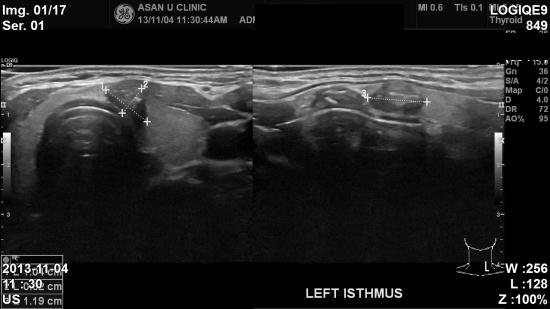

아산유외과 개원 후 9번째 갑상선암 진단.

갑상선 혈액검사만 받아보시다 직원분 권유에

생에 처음으로 초음파를 하시게된 59세 여자분이십니다.

검사결과 갑상선에 혹이있어 본원으로 의뢰받으셨고,

미세침흡입검사결과 갑상선 유두암으로 진단되셨습니다.